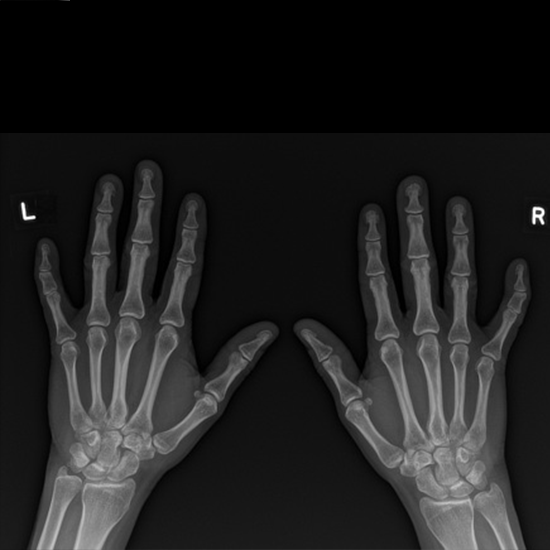

X-ray Both Hand AP & LAT

What is an X-ray Both Hand AP LAT Test?

An X-ray of the hand shows the bones of the hand and the soft tissues (skin and muscles) around it.

Why is it done?

• To diagnose infections, osteoporosis, bone abnormalities, and arthritis (inflammation of the joints).

• To diagnose hand fractures and monitor healing.